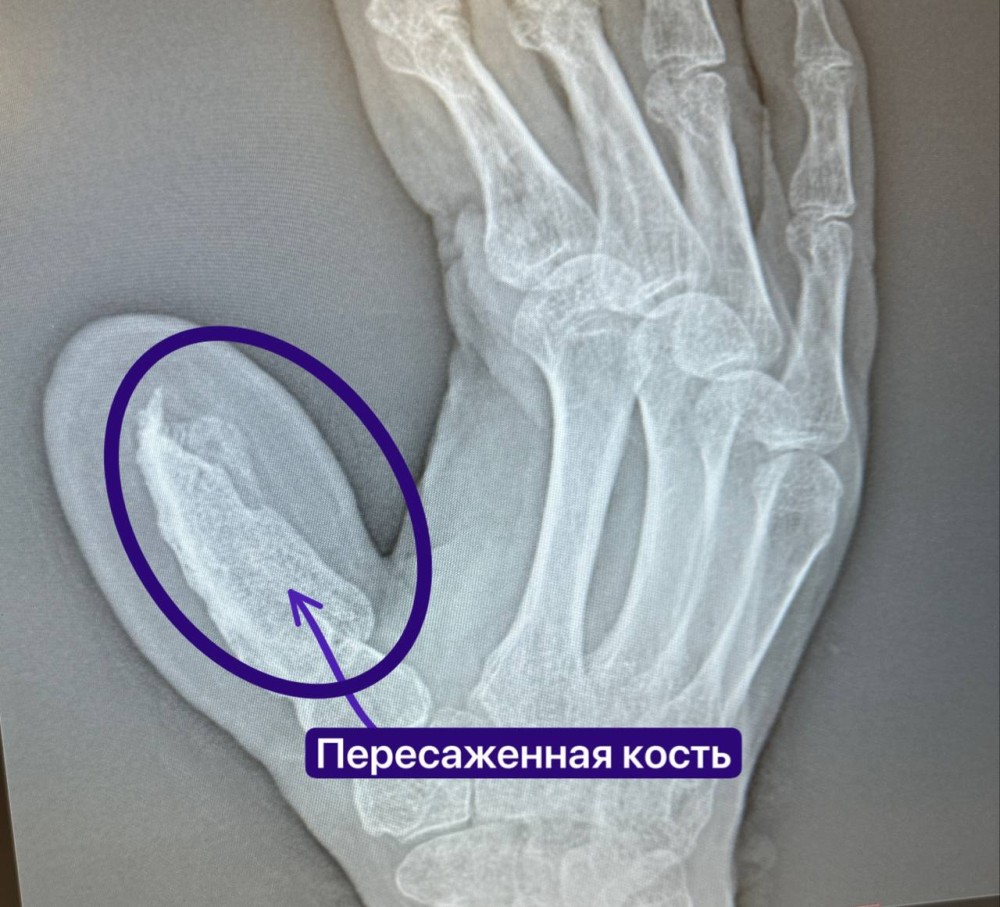

Первым этапом мужчине пересадили пятисантиметровую кость с гребня подвздошной кости вместе с артерией огибающей подвздошную кость и подшили руку к животу, чтобы обеспечить кровоснабжение будущего пальца. Мужчину около 4 часов оперировали в отделении травматологии №2 микрохирурги Руслан Тельманович Радьков и Эльвира Рафиковна Кадырова.

Следующие 1,5 месяца пациент ожидал, пока кость приживется, адаптируясь к жизни с некоторыми ограничениями.

Следующим этапом хирурги отсекли руку от живота и снова отпустили пациента домой, чтобы все зажило. Далее было две операции по удалению лишней кожи и подкожно-жировой клетчатки, чтобы сформировать форму будущего пальца.

В последнюю госпитализацию пациенту пересадили лоскут с нервными окончаниями, чтобы вернуть чувствительность новому пальцу. Все прошло успешно.